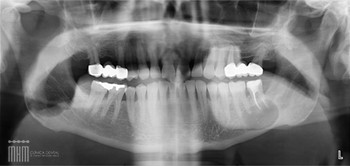

Como se descubren ?. En el 90% de los casos mediante una exploración radiográfica rutinaria aunque a veces producen síntomas que nos pueden ayudar a diagnosticarlos.

Los Quistes de los dientes sin erupcionar: Quiste dentigeno. Son los quistes foliculares y se presentan en los dientes que no han erupcionado principalmente en los molares del juicio aunque también los vemos en caninos

Quiste radicular. Es el más frecuente de todos los quistes.

Suele situarse en la raíz de los dientes y puede producir un proceso inflamatorio, absceso dental, celulitis y a veces crear fistulas en la boca por la que expilsan el contenido del mismo.